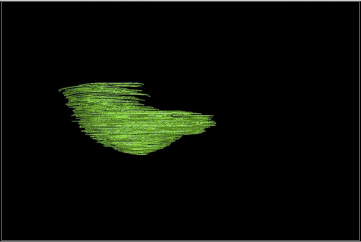

A handheld Artec 3d scanner was used to capture the patient’s chest in anm upright position (Fig. 4). The scanned data was imported into Artec Studio software, where the breast region was carefully segmented using manual and automatic boundary selection tools to isolate it from surrounding tissues. The Measures tool in Artec Studio was then used to compute the volume of the segmented breast model directly (Fig. 5).

Figure 5. The volume of the segmented breast model computed using Artec Studio.